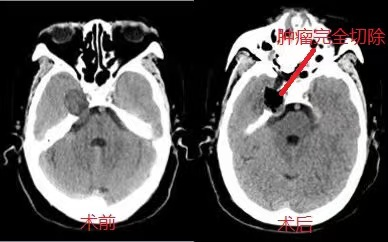

患者复查颅脑MR平扫+强化提示“右侧中颅窝肿瘤增大,向后侵犯后颅窝”。神经外五科团队术前讨论认为,该病例按常规方法可选择颞下入路开颅肿瘤切除术,但鉴于该病灶位于中颅底内侧,累及Meckel’s囊,以选择经鼻内镜下肿瘤切除术为更好。

经充分术前准备后,在科主任王喆带领下采取经鼻-筛-翼突入路侧颅底肿瘤切除术。术中磨除部分上颌窦,翼突和蝶窦骨质,依据解剖结构精确定位,直抵病灶,切开硬脑膜后,细致地分离并分块切除肿瘤,保护三叉神经,小心地分离肿瘤与颈内动脉地粘连,发现肿瘤起源于三叉神经半月节,与其粘连紧密。肿瘤切除后,空腔填塞患者自体脂肪,以鼻中隔粘膜瓣进行颅底重建,鼻腔填塞碘仿纱条。患者恢复顺利。